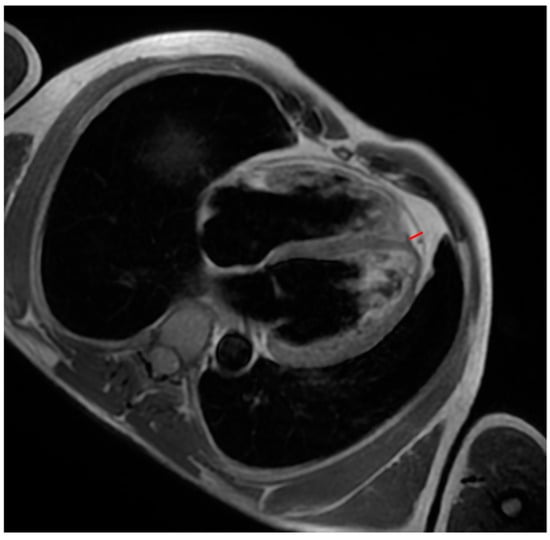

All patients underwent CMR on a 1.5-T whole-body scanner. The CMR protocol included the following: (a) breath-holding steady-state free precession (SSFP) sequences (short axis covering the entire LV and 2-, 3-, 4-chamber long-axis views, RV inflow, sagittal RV outflow tract) for functional analysis and quantification of ventricular volumes and ejection fraction; (b) black-blood T1-weighted imaging to assess fat infiltration; (c) late gadolinium enhancement (LGE) imaging according to our protocol; and (d) T1 mapping sequences. Image processing was performed by two observers (F.M./E.T.) with more than 2 years of cardiac imaging analysis experience. For each CMR image, contours were manually created to segment fat in the epicardium. EAT thickness was measured in the best sequence (SSFP or black-blood T1-weighted sequence) (Figure 1), according to a previously published method [12].

Figure 1. A patient with ACM. Black-blood T1-weighted 4-chamber image shows an example of measuring interventricular groove EAT (red line).